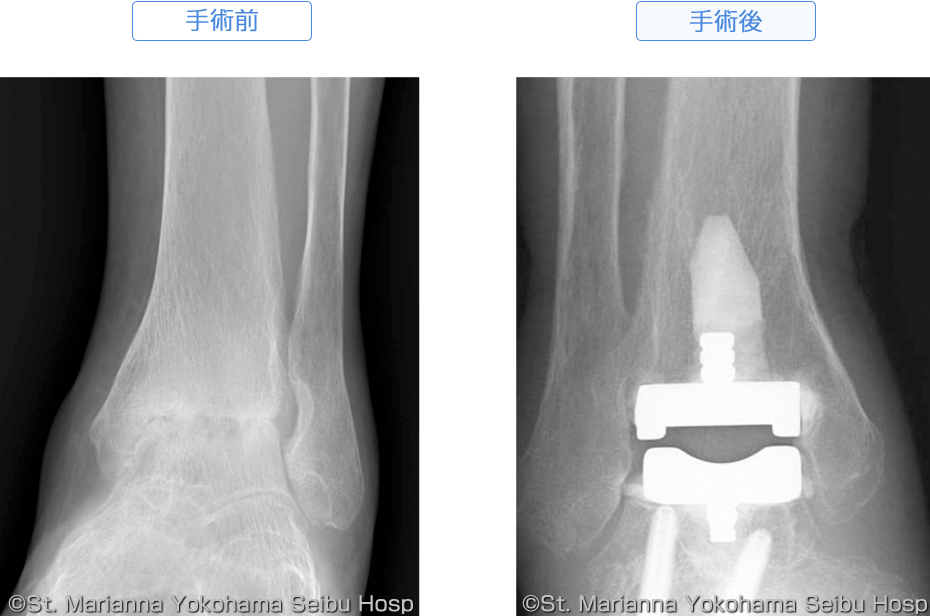

「足部・足関節の手術」松田 秀一定価: ¥ 12000#松田秀一 #松田_秀一 #本 #自然/医療・薬学・健康裁断済みです。新品を業者にお願いしたので、書き込みもなく綺麗なままです。